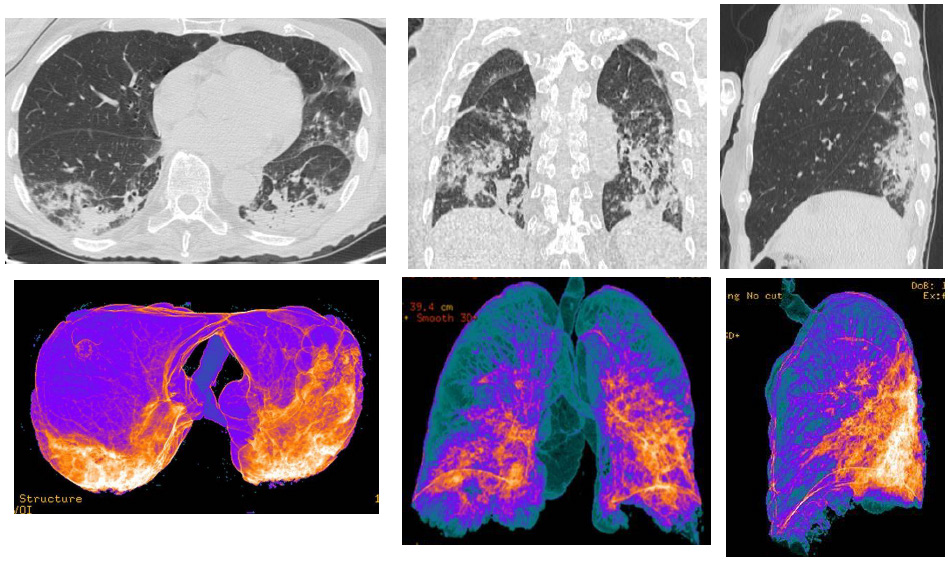

Figure 2: CT patterns of extended bilateral Covid-19 pneumonia of a 80-year-old male patient. MPR (axial, coronal, sagittal) reconstructions showed: bilateral and multifocal typical “ground-glass” areas; bilateral interstitial thickenings, with some consolidations areas; bi-basal pleural effusion. In the Volume Rendering (VRT) “colored” reconstructions, the blue areas represented the normal lung parenchyma (also in the ventral and dorsal areas), while orange/white and red areas indicate the inflammatory pulmonary involvements, with consolidations.